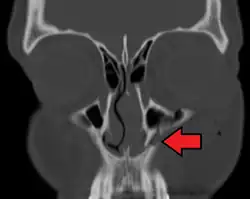

![]() Position of the maxilla | |